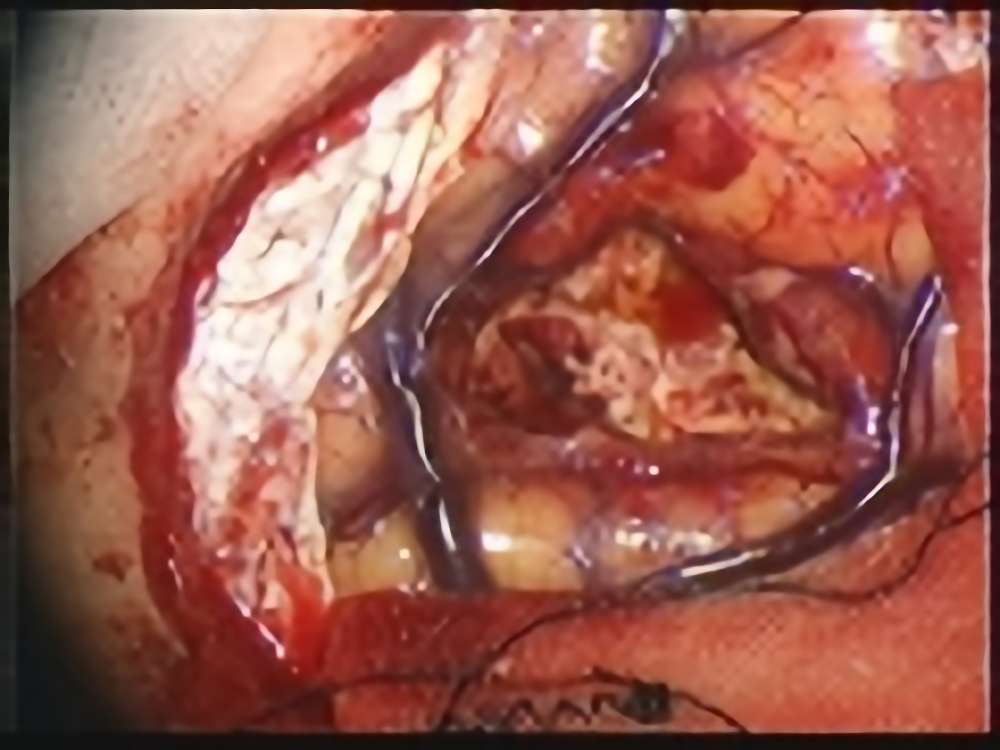

術中写真

摘出 前

摘出 中

摘出 後